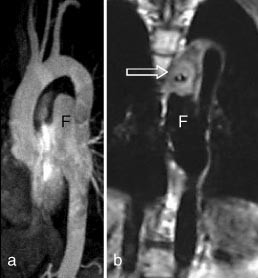

Aortaaneurismer fremstilles som regel adekvat med både CT og MR. Kontrastforsterket MRA har den svakhet (i likhet med kateterangiografi) i forhold til CT at bare karlumen og ikke trombemassene vises. Konvensjonell MR kan imidlertid vise trombene (fig 7).

Intraabdominale kar

Kontrastforsterket MRA representerer et betydelig fremskritt for MR-diagnostikken av intraabdominal karanatomi. Metoden har potensial til å overta mye av kateterangiografiens diagnostiske rolle i dette kargebetet. I diagnostikk av signifikant nyrearteriestenose har metoden sensitivitet og spesifisitet på godt over 90 % ved sammenlikning med kateterangiografi (16 – 18). MRA vil kunne utelukke signifikant stenose i de største nyrearteriene, men metoden gir fortsatt for dårlig fremstilling av de intrarenale grener. Ved hypertensjon hos yngre personer der man kan mistenke fibromuskulær dysplasi, bør det derfor fortsatt gjøres kateterangiografi. Kontrastforsterket MRA har ikke minst vist seg nyttig hos nyre- og levertransplanterte pasienter (19). Ved mistanke om arteriestenose vil metoden kunne selektere de pasienter som bør utredes videre med kateterangiografi før ev. ballongdilatasjon av stenosen (fig 8). Ved å gjøre flere MRA-opptak etter samme kontrastmiddelbolus kan både arteriefase og venefase fremstilles separat, noe som er særlig nyttig ved utredning av levertransplantater (fig 9). Den gode fremstillingen av sentrale arterier og vener gjør metoden også egnet ved vurdering av tumoroperabilitet i lever og pancreas.